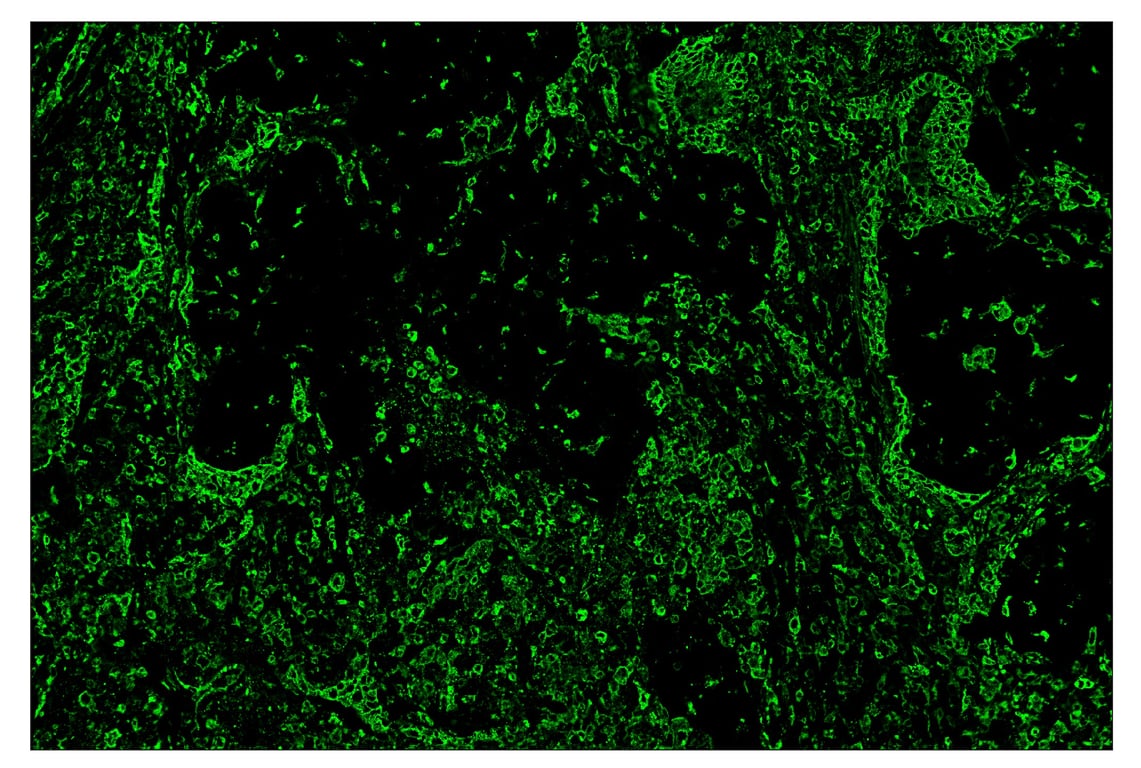

SignalStar™ immunohistochemical analysis of paraffin-embedded human squamous cell lung carcinoma using HLA-DRA (E9R2Q) & CO-0023-488 SignalStar™ Oligo-Antibody Pair #92941 (green). All fluorophores have been assigned a pseudocolor, as indicated. Staining was performed on the BOND RX by Leica Biosystems.

Immunohistochemistry Image 2: HLA-DRA (E9R2Q) & CO-0023-647 SignalStar<sup>™</sup> Oligo-Antibody Pair